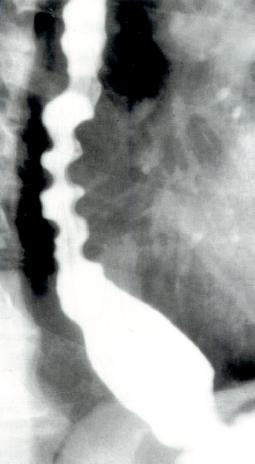

胡桃夹食管病因不明,多认为是原发性食管运动障碍疾病发展过程中的一部分,很可能是弥漫性食管痉挛的先兆。

Blackwell(1984)推测本病最终将发展为贲门失弛缓症,认为其发病与对酸反流的反应有关,还与精神心理因素及痛阈降低有关,精神和心理因素可诱发本病胸痛症状发作。病人常伴有抑郁、焦虑等表现。同时,食管动力学的变化也与精神受刺激有一定关系。但未发现明确的病理学改变。胡桃夹食管与弥漫性食管痉挛、贲门失弛缓症及胃食管反流的关系值得进一步研究。Blackwell(1984)认为其相互之间可能存在以下转化关系。